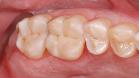

Fertige Füllung vor Politur:

Nach dem Einbringen des Kompositmaterials wird die Füllung anatomisch geformt und angepasst.

Polierte Kompositfüllung: Nach der Aushärtung wird die Füllung auf Hochglanz poliert, um eine glatte Oberfläche zu gewährleisten, die Plaqueablagerungen minimiert und für ein angenehmes Mundgefühl sorgt.